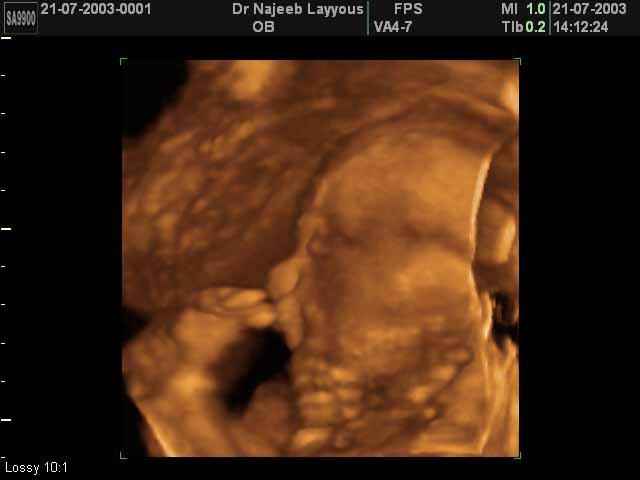

- 3D Fetal Profile Ultrasound Scan Photos